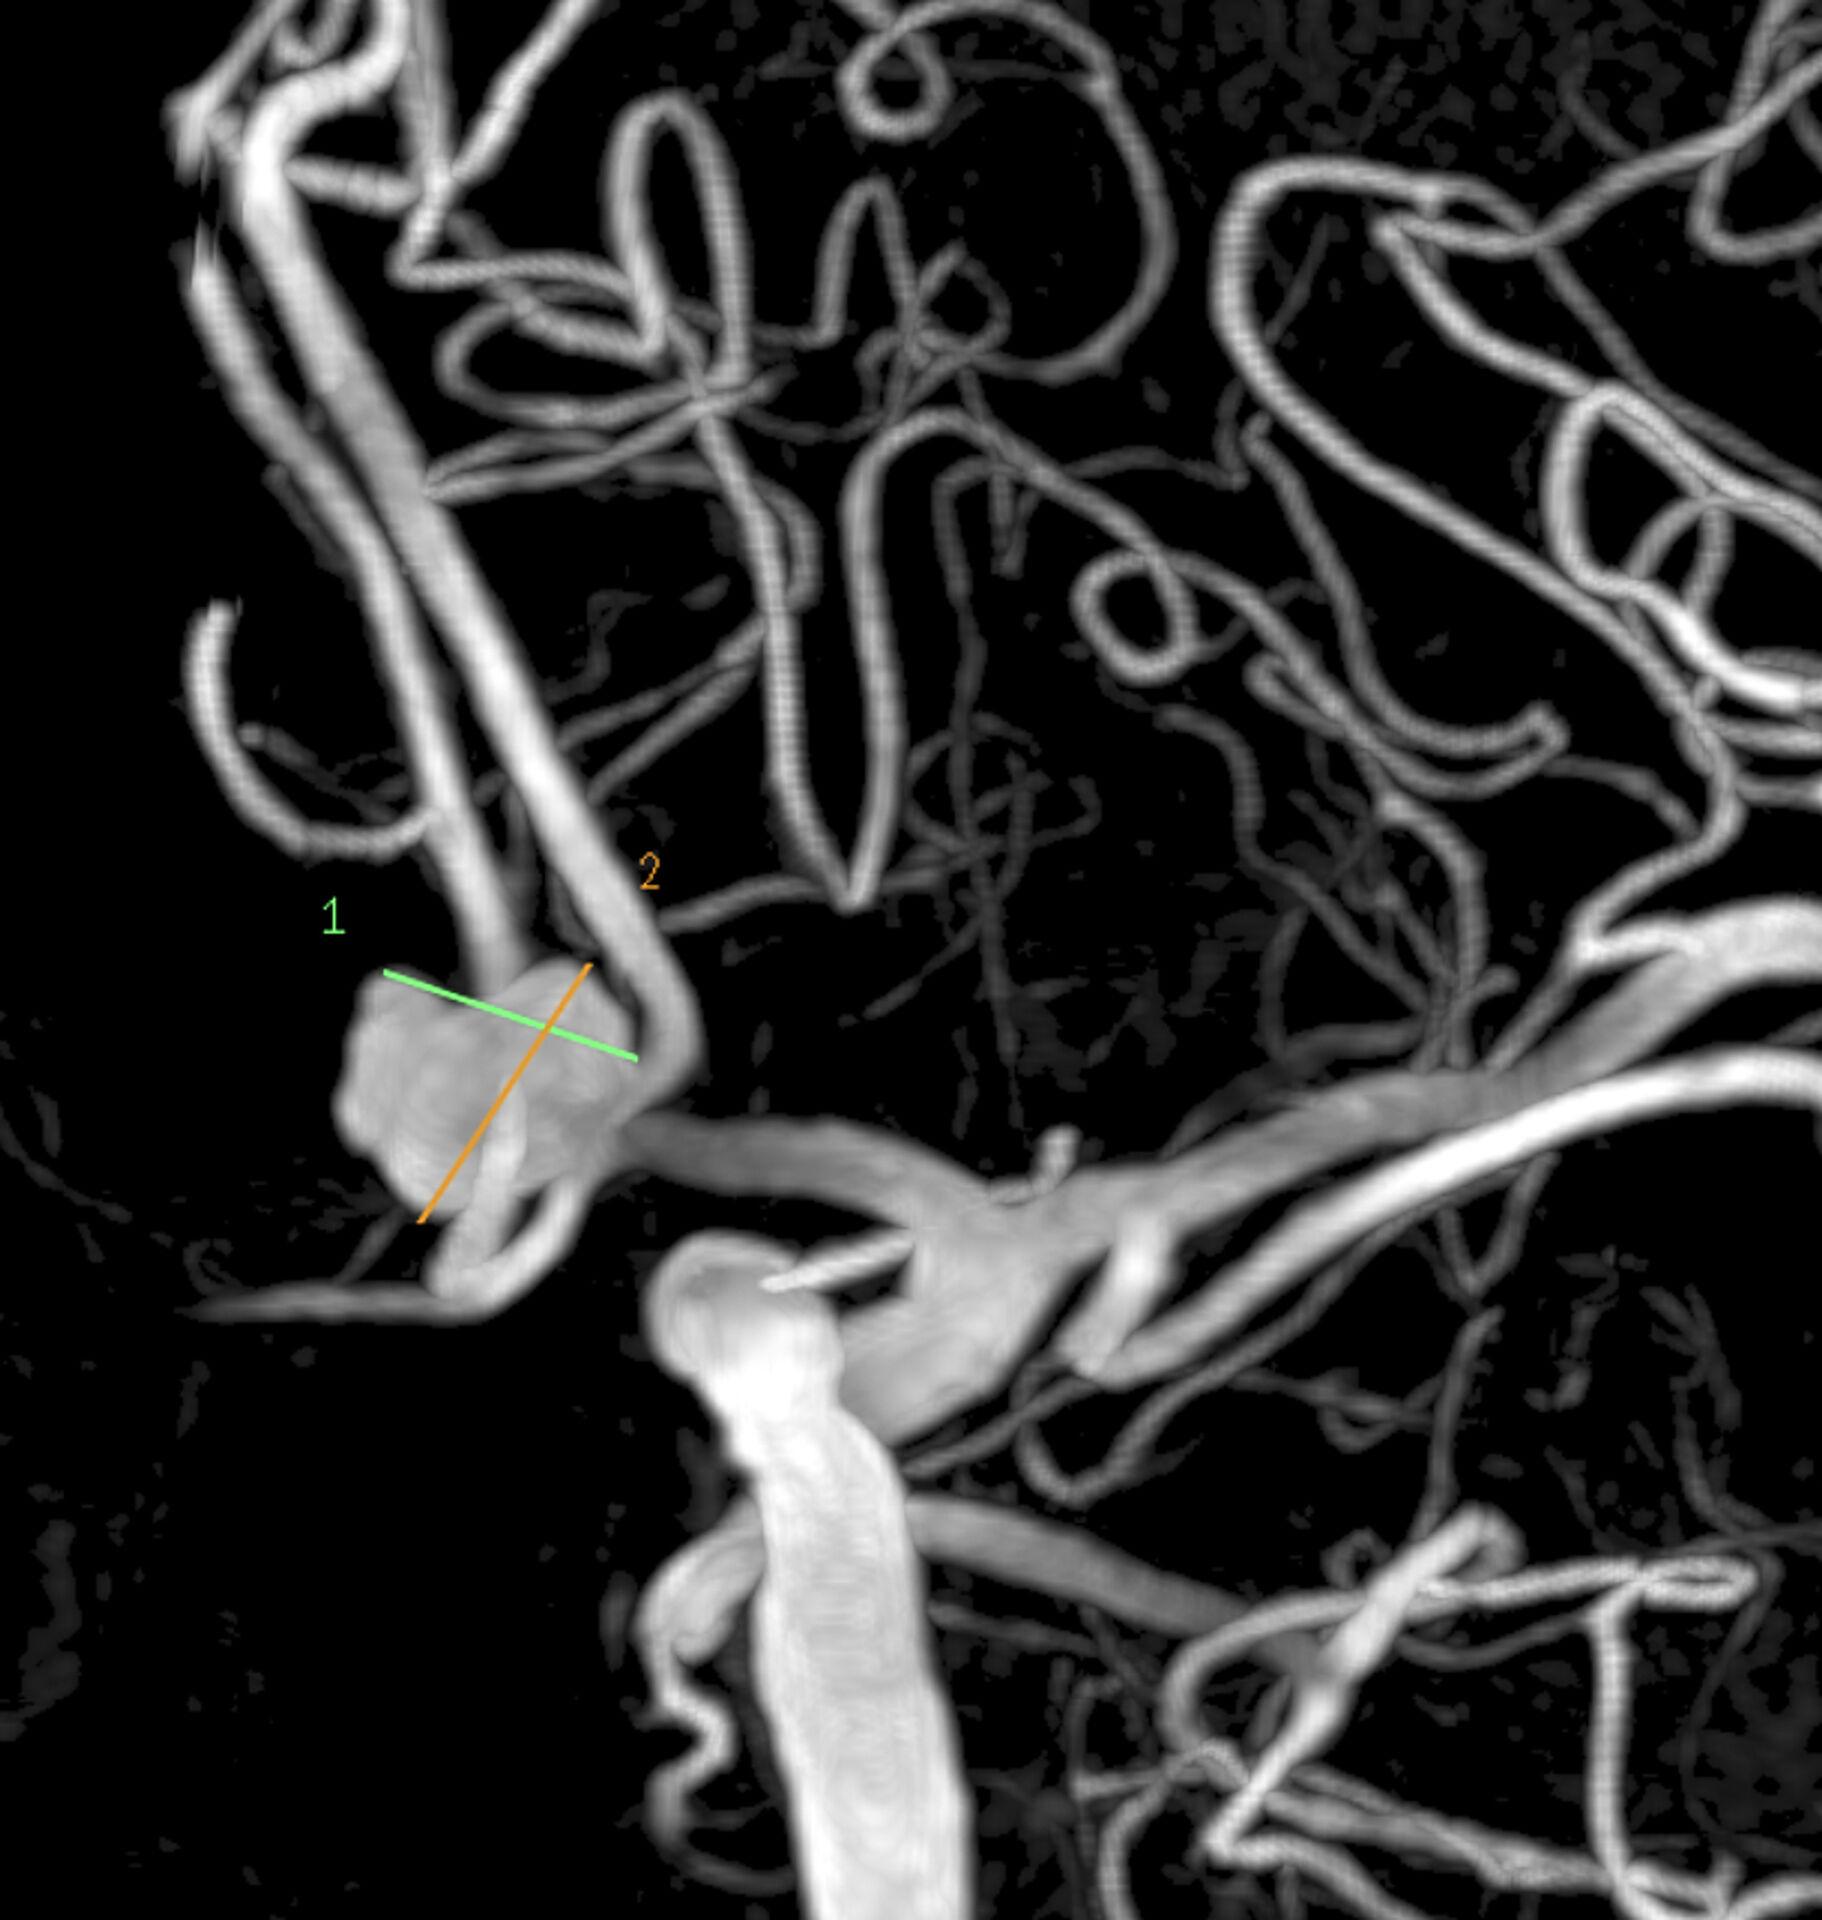

L’anévrisme intracrânien est une dilatation anormale de la paroi d’une artère cérébrale. Il peut se former progressivement sous l’effet d’une fragilisation de la paroi vasculaire, favorisée par des facteurs tels que l’hypertension artérielle, le tabac ou certaines prédispositions familiales. Souvent silencieux, il peut être découvert fortuitement lors d’un examen d’imagerie, mais parfois se manifester par des maux de tête, des troubles visuels ou des signes neurologiques localisés. Le risque majeur reste la rupture, responsable d’une hémorragie méningée, une urgence neurochirurgicale pouvant mettre en jeu le pronostic vital.

Le diagnostic repose sur l’imagerie cérébrale. L’angioscanner, l'angio-IRM et surtout l'artériographie cérébrale permettent de visualiser la taille, la forme et la localisation de l’anévrisme. En cas d’hémorragie méningée, une ponction lombaire ou un scanner cérébral peuvent confirmer la présence de sang dans les espaces méningés. Le bilan est ensuite discuté en réunion de concertation pluridisciplinaire associant neurochirurgiens, neuroradiologues et réanimateurs afin de définir la stratégie thérapeutique la plus adaptée.

Selon la nature et la localisation de l’anévrisme, plusieurs options thérapeutiques sont possibles. Le traitement endovasculaire, réalisé par les neuroradiologues interventionnels, consiste à occlure l’anévrisme par la pose de coils ou de stents, sans ouverture chirurgicale. Lorsque cette approche n’est pas indiquée, une chirurgie conventionnelle de clipping est proposée, consistant à placer un clip métallique sur le collet de l’anévrisme afin d’en prévenir la rupture.